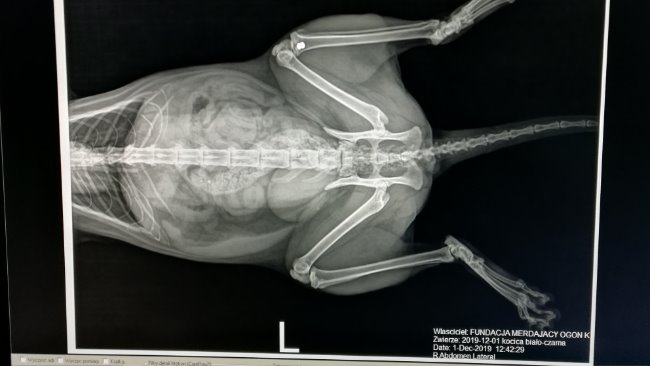

Dwa miesiące temu Piratka zaczęła lekko utykać na tylna łapkę. Jej karmicielki myślały, że to chwilowe i faktycznie po jakimś czasie przeszło. Niestety kilkanaście dni temu Piratka przestałą stawać na przednią łapkę :( Widać było, że coś jest nie tak. W końcu udało się ją złapać, trafiła do lecznicy i wszystko okazało się jasne. Piratka stała się dla kogoś żywą tarczą!!!! I to nie był jednorazowy incydent, nie strzelano do niej zwykłymi kulkami śrutu. Strzelano, żeby zabić!!!

Przednia kość całkiem roztrzaskana :( W drugim przednim ramieniu śrut.

W tylnej łapce również śrut :(